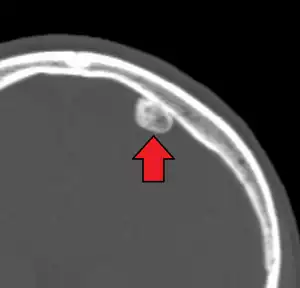

| CT scan showing an osteoma growing on inside of skull bone | |

Medical imaging such as X-ray, CT scan and MRI show dense, clearly defined, round white tumors attached to bone.[1] They may be diagnosed when having medical imaging for another reason.[3] Osteomas of the paranasal sinuses and skull base can be diagnosed using CT-scan without intravenous contrast, allowing its size and relation to nearby important structures to be assessed.[3] A biopsy is not usually required.[3]

CT-scan skull: Osteoma of the frontal sinus